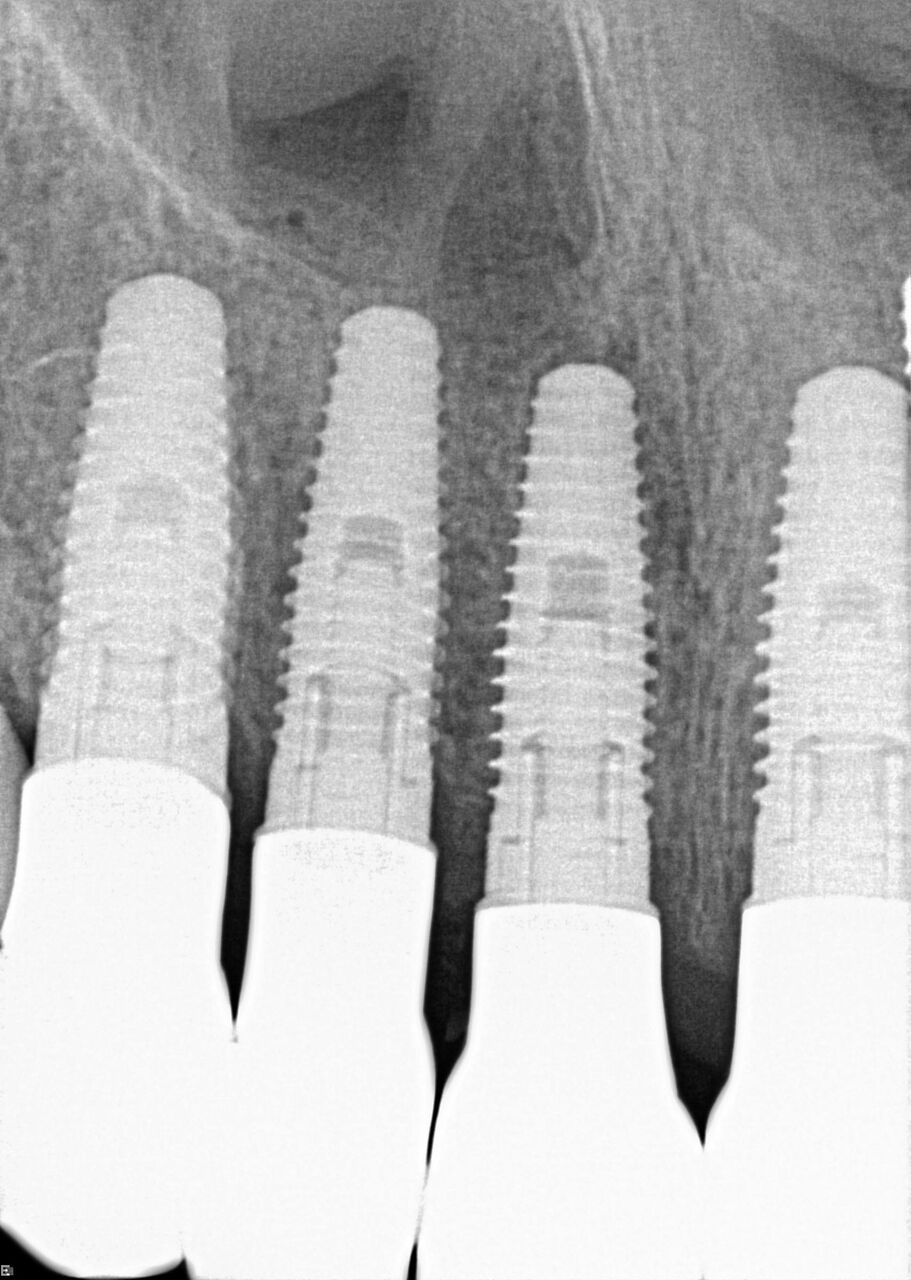

(17.) Case 3 initial radiograph of bridge on Nos. 6 through 9 and crown on No. 10.

Figure 17

(18.) Case 3 initial radiograph of bridge on Nos. 6 through 9 and crown on No. 10.

Figure 18

A 42-year-old man presented with a very loose bridge on Nos. 6 through 9 with periodontally compromised retainers on Nos. 6 and 9 (Figure 17 through Figure 19), and endodontically involved No. 10 with a calcified canal. Teeth Nos. 6, 9, and 10 were extracted, the sockets fully debrided, and pontic soft tissue on Nos. 7 and 8 sculpted to be symmetrical in soft tissue contour with the contralateral lateral incisor and central incisor locations. Implants were secured in position Nos. 6 through 10 (Figure 20) in excess of 45 Ncm, the bone was milled to provide unimpeded seating of temporary abutments, and temporary crowns were fabricated chairside and adjusted to be out of occlusion in centric relation and all excursions. The temporary crowns were cemented after extrusion of excess cement extraorally and the patient was prescribed antibiotics, analgesics, and instructed in postoperative care particular to immediately provisionally restored implants. At 6 months, integration was confirmed (Figure 20 through Figure 23) and after placement of scanning abutments, the implants and soft tissues were scanned. Final crowns were fabricated from the scanned images and were cemented after extrusion of excess cement extraorally (Figure 24 through Figure 26), and oral hygiene procedures were reviewed.